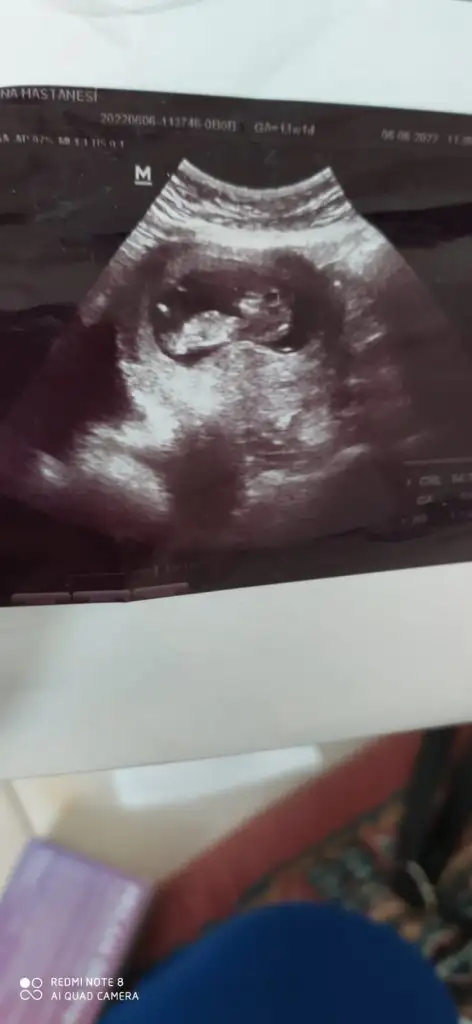

Merhaba 7 buçuk haftalık tahmin ederseniz sevinirim☺️

Eklentiler

• IMG-20220628-WA0005.webp

IMG-20220628-WA0005.webp

21,7 KB · Görüntüleme: 67